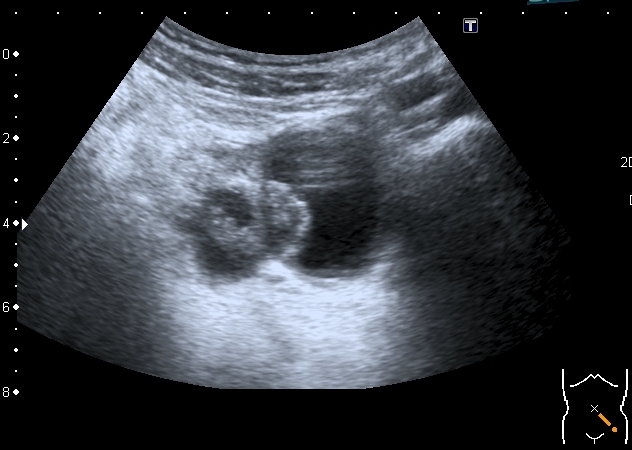

Сходные по структуре образования в левом яичнике

Высказал предположение о множественных папиларных цистаденомах яичников. Хотелось бы узнать, насколько я прав.

Думаю, что на папиллярную цистаденому это похоже.

Никогда не встречал мультилокулярное и билатеральное поражение , но покопавшись в книгах, вычитал, что двухстороннее поражение составляет от 6 до 32% случаев. Очень подходит клиника - боли в животе, увеличение живота, дизурия. Дальнейший прогноз - 50% малигнизация.